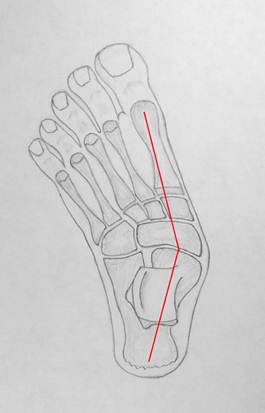

Движения

в стопе осуществляются вокруг её оси. Ось стопы проходит от пяточного бугра

через центр таранно – ладьевидного сустава к головке 1 плюсневой кости. В

прямой проекции она имеет практически прямую форму, а в боковой проекции ось

стопы изогнута в области таранно – ладьевидного сустава в подошвенном

направлении. Своё естественное положение оси стоп занимают только в положении

стоя, потому их исследование выполняется у стоящего человека. Форму оси стопы в

прямой проекции отражает её внутренний край – он в номе практически прямой.

Нормальная

стопа под нагрузкой в виде сверху, её

изображение совмещено с изображением скелета. Красная линия обозначает ось

стопы, зеленые точки обозначают опорные точки, через которые ось стопы

проходит: центр пяточного бугра, центр таранно – ладьевидного сустава и головку

первой плюсневой кости.

Вы

можете заметить минимальную, в несколько градусов, вальгусную деформацию оси,

что является нормальным явлением.

Внутренний край стопы, который отражает состояние её оси в прямом виде,

остается ровным. Это свидетельствует о нормальной форме оси стопы в прямом

виде.